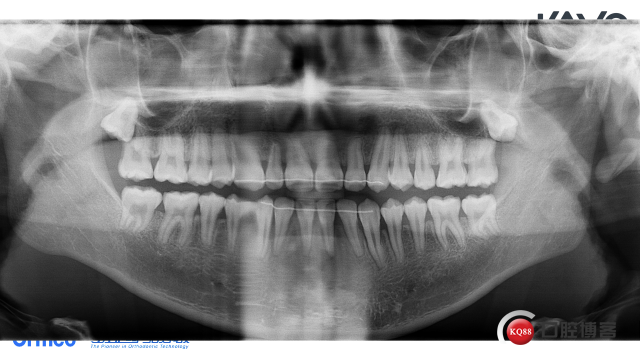

初诊全景片:智齿牙胚存,38,48牙冠基本发育正常,位置较正,髁突右侧略大于左侧,下颌升支无明显不对称。